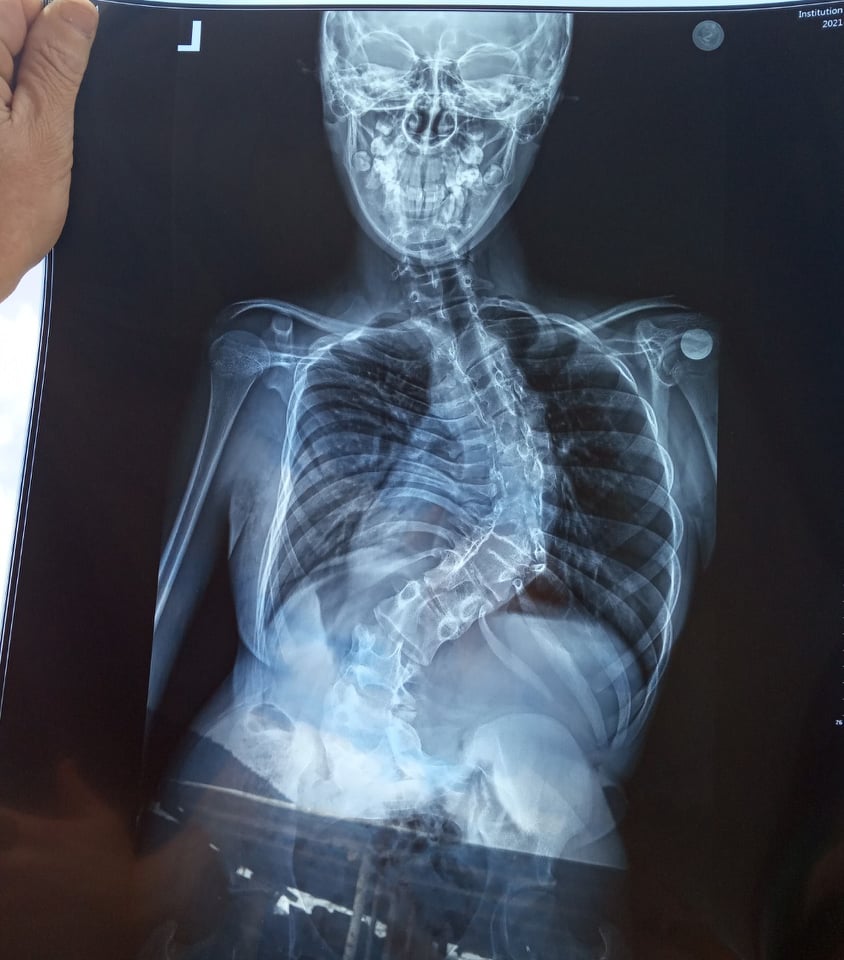

14-річна Тетяна Бабич із села Смеречка, що у Самбірському районі, потребує негайної дорогавартісної операції. У дівчинки вроджена вада хребта, зрослися хребці грудного та поперекового відділів. Від такого викривлення, Тетянці стискає легені, вона терпить невимовний біль. Допомогти може лише оперативне втручання, на яку дуже потрібні гроші.

Як пояснюють лікарі матері дівчинки – у неї вроджена аномалія хребта – зрощення хребців у грудному та поперековому відділах, простіше кажучи хребет поступово викривляє буквою «s». Крім того  у Тетянки у двох місцях зрощені по два ребра. Вся ця проблема не дає дитині дихати, тисне на легені. Дівчинка відвідує звичайну школу, але з кожним днем її дається це важче.